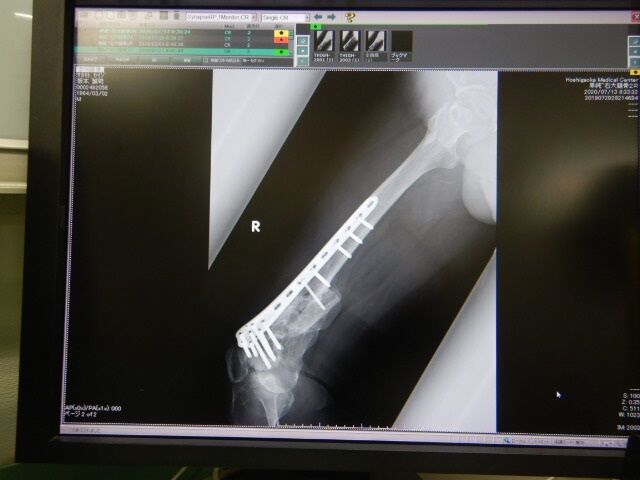

±¦Âǯ¼¡ÅÀ¸¡¤Ø¹Ô¤Ã¤Æ¤¤Þ¤·¤¿¡£±¦²èÁü¤«¤é2018ǯ¡¢2019ǯ¤È¤Ê¤ê

º¸¤Î¥ì¥ó¥È¥²¥ó²èÁü¤¬2020ǯº£Æü¤Î

±¦Â¤Î¥ì¥ó¥È¥²¥ó²èÁü¤Ë¤Ê¤ê¤Þ¤¹¡£